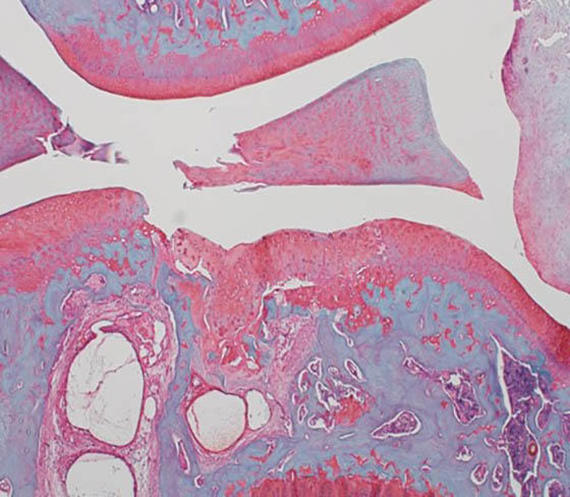

Model knee joint showing diet-induced metabolic osteoarthritis

Osteoarthritis (OA) is a painful condition where the cartilage in a joint degenerates. Obesity, which causes low grade inflammation in the body may worsen OA. In studies with animal models, BME researchers have shown that a diet high in fat and sugar leads to more body fat, inflammation in the knee joint and elsewhere and ultimately, joint damage and knee OA within 12 weeks.